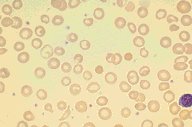

This is a high dry view of a Wright's stained peripheral blood

smear from a patient with iron deficiency anemia. A normal

lymphocyte for comparison purposes is seen in the corner of the

photograph. Significant hypochromia and microcytosis is seen, as

well as moderate variation in size and shape of the red cells.